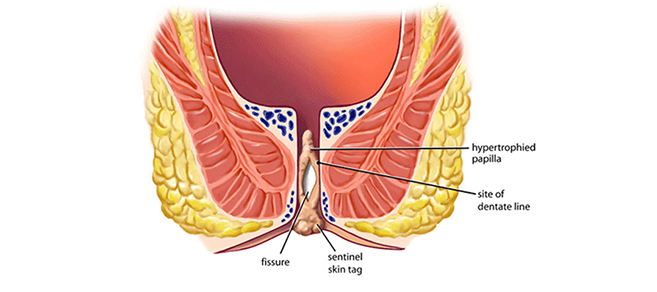

A fissure is a tear of the skin at the edge of the anus. It can cause pain, bleeding and/or itching.

Fissure can be acute (new) or chronic (persistent).

Sometimes an anal Fissure and a hemorrhoid develop at the same time.

Most health professionals can diagnose an anal Fissure by listening to the symptoms and by looking at the anus. Usually, the health professional can see the Fissure by gently separating the buttocks.